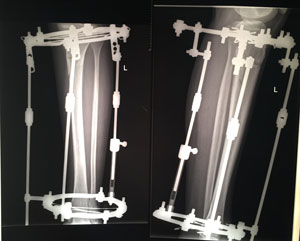

Дата операции - 07.05.2019г.